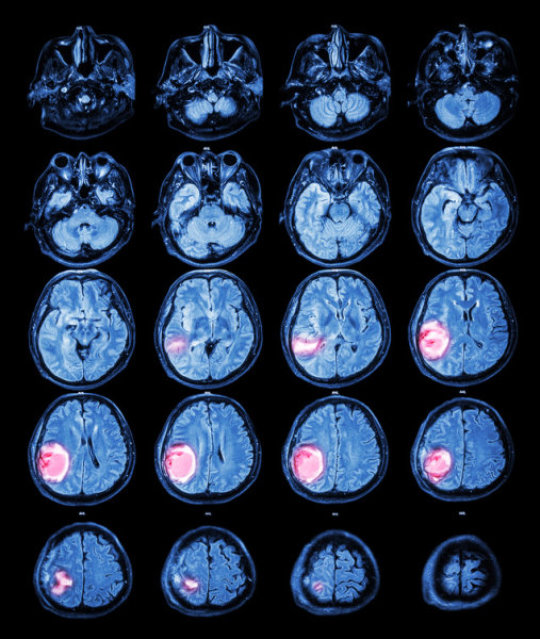

“当我21岁时,他们在我的大脑中发现了一个肿块,我很快进行了切除手术,但是切片结果显示这是阳性的,”现年26岁的Lisa Rosendahl说,她患上了转移性胶质母细胞瘤,这是大脑很常见的原发性恶性肿瘤,预后很差。为了治疗这一疾病,Lisa尝试了很多种方法,癌症出现了化疗抗性,她的医生对她说只有几个月的时间了。

研究人员进一步分析发现,癌细胞中基因BRAF发生了突变,尤其是BRAFV600E,这一基因与自噬密切相关,除了最初发现这一突变的黑素瘤之外,上皮胶质母细胞瘤也很有可能携带了BRAFV600E突变。

研究人员已经知道Lisa肿瘤对于BRAFV600E突变是阳性的,这标志着肿瘤特别依赖于自噬,而且目前传统的临床实验已经不再适合她,因此他们决定给Lisa的治疗中加入抑制自噬的药物氯喹。